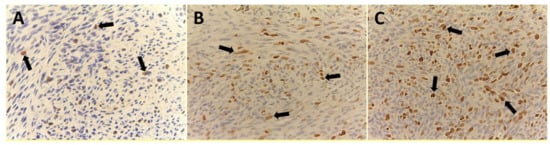

| No. of Patients (%) | MVD ×400 | EA ×400 | Ki-67 Index in Terms of MIB-1 Positive Nuclei ×400 |

| G1 (32/99–32.3%) | 9 ± 4 | 81.96 × 10−2 ± 20.30 μm2 | 9.35 ± 5.82 |

| G2 (38/99–38.4%) | 12 ± 5 | 83.01 × 10−2 ± 25.48 μm2 | 15.16 ± 8.91 |

| G3 (29/99–29.3%) | 25 ± 9 | 151.77 × 10−2 ± 33.52 μm2 | 44.33 ± 17.91 |

| ANOVA test | G1 vs. G2 | G1 vs. G2 | G1 vs. G2 |

| n.s. | n.s. | n.s. | |

| G1 vs. G3 | G1 vs. G3 | G1 vs. G3 | |

| f = 282.80 | f = 288.75 | f = 340.83 | |

| p = 3.53 × 10−24 | p = 2.12× 10−24 | p = 3.41 × 10−26 | |

| G2 vs. G3 | G2 vs. G3 | G2 vs. G3 | |

| f = 196.54 | f = 247.24 | f = 214.29 | |

| p = 2.53 × 10−21 | p = 7.79. × 10−24 | p = 2.97 × 10−22 |